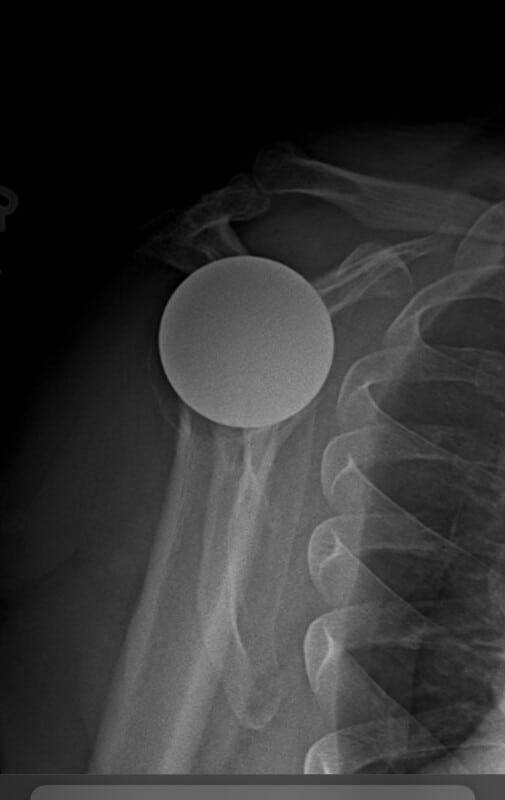

Shoulder Innovations, Inset